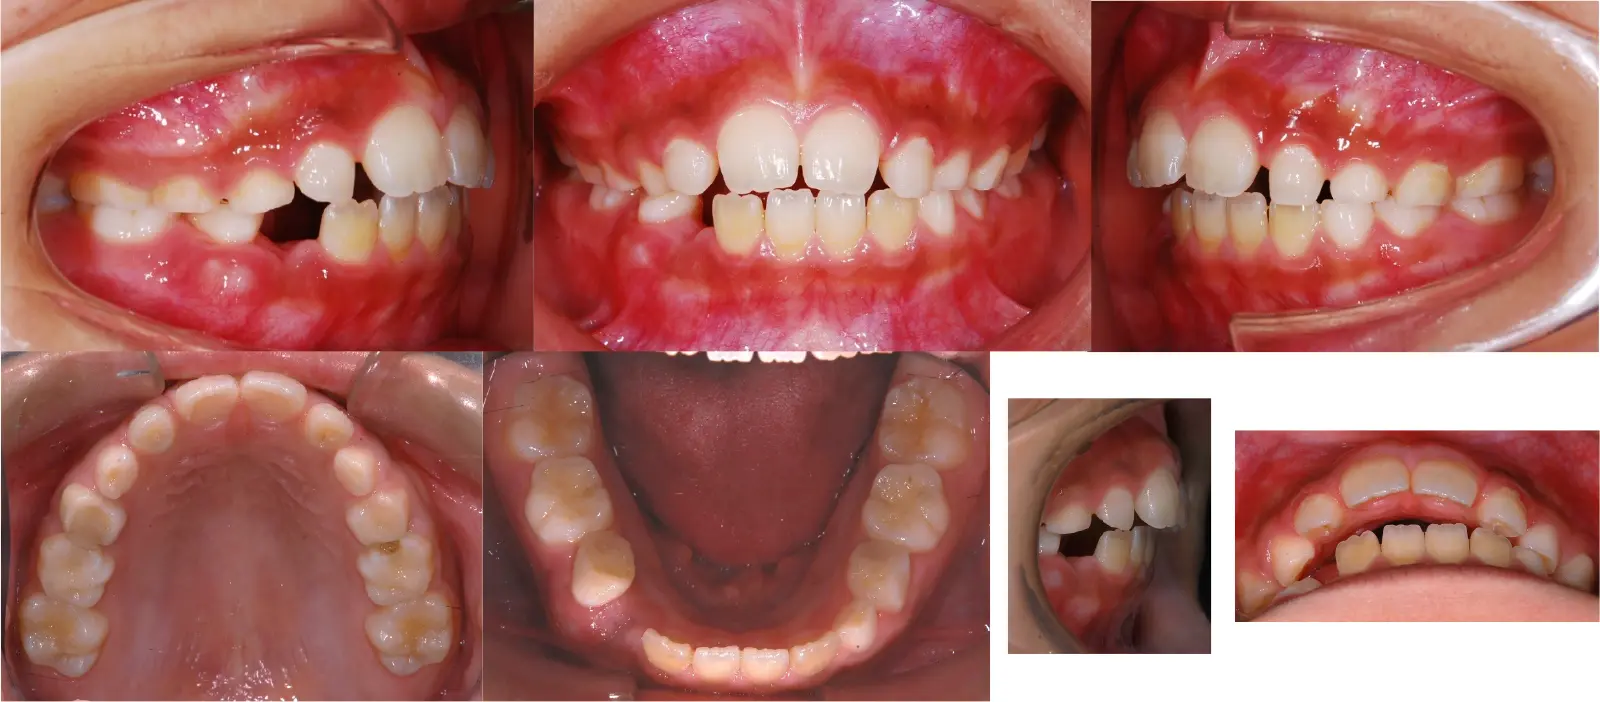

アングルⅡ級 軽度叢生を伴う下顎前突症

第一段階の治療のみで、

永久歯は問題なく萌出し、安定している

- 主訴

歯のガタガタと切端咬合

- 年齢

8歳

- 治療期間

1年3ヶ月

- 治療回数

7回

- 治療に用いた主な装置

2by4、フェイシャルマスク、拡大床

- 治療費

400,000円(税別)トータル料金

- 抜歯部位

非抜歯